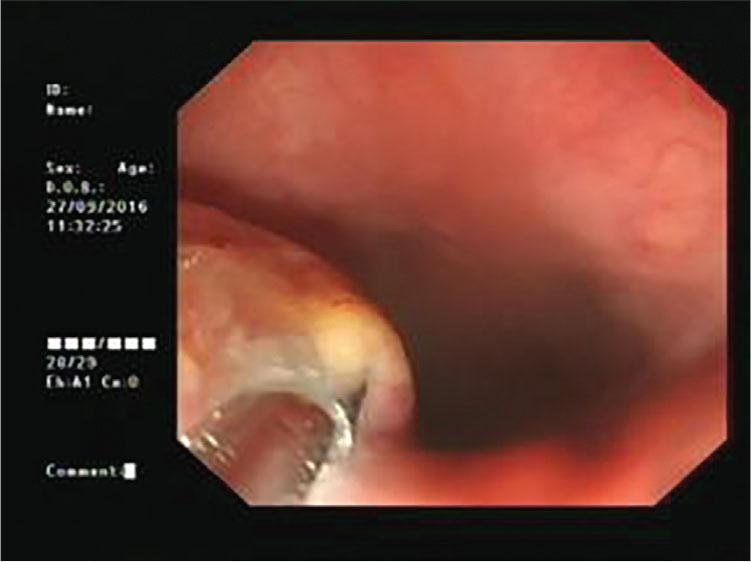

On September 23, 2016, a 56-year-old man consulted the emergency department for 7 days with unknown fever. The highest temperature was 38.5°C. Blood tests were as follows: WBC 7.75 × 109/L, NEUT 76.94%, CRP 120.57 mg/L, and procalcitonin 0.325 ng/ml. Posterior superior mediastinal masses with thickened adjacent esophagus wall and bilateral pleural effusion were revealed by thoracic computed tomography (CT) scan (Figure 1). A 1.0 cm × 2.0 cm protuberant mass was found in the left wall of the esophagus at 20 cm from the incisors by the gastric endoscopy (Figure 2). Endoscopic biopsy shows a chronic active inflammation with ulcer and granulation tissue proliferation. Examine the medical history in detail at that moment, the patient was diagnosed with an odynophagia and admitted that he had accidentally swallowed a fishbone 2 months ago. Taken together, the patient was diagnosed with secondary mediastinitis due to esophagus perforation caused by the ingestion of fishbone. The patient had been treated moxifloxacin intravenously for 15 days, and then he was discharged without fever. Obvious back pain and decreased muscle strength began on the 7th day after discharge. On November 10, he had a Magnetic resonance (MR) of the thoracic vertebra, and the result was C7/T1 centrum infection and paravertebral abscess (Figure 3). The surgical intervention had been performed 4 days later. Consequently, the back pain disappeared, the muscle strength recovered, and an MR reexamination showed the patient recovered completely (Figure 4).

Figure 2

The gastric endoscopy result.